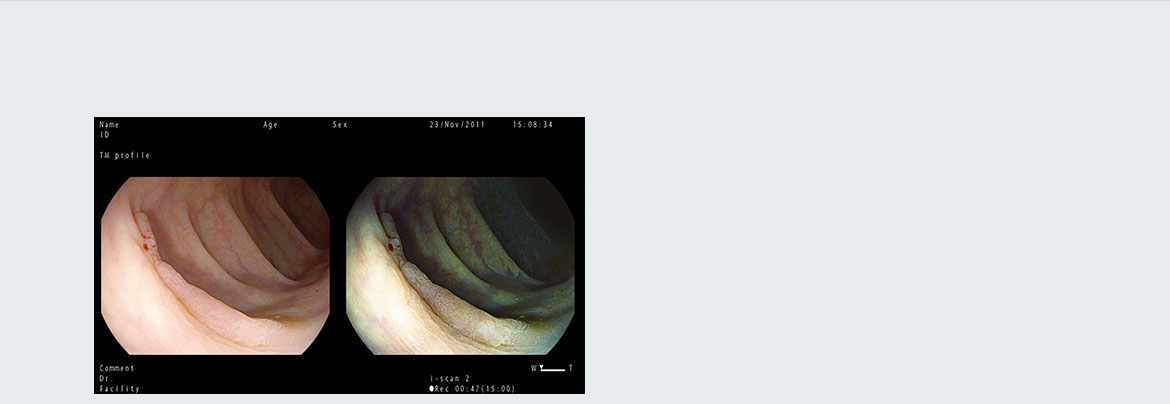

Режим одночасного показу двох зображень Twin

Два зображення одночасно на великому моніторі дозволяють ендоскопістам вивчати та порівнювати специфічні особливості уражених тканин, користуючись налаштуваннями режиму i‑scan та збільшенням.